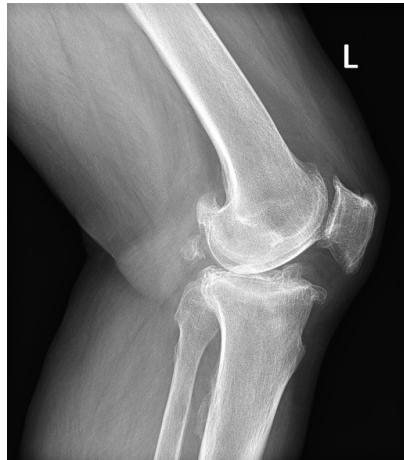

AP HIP Joint line narrowing, osteophyte formation, subchondral sclerosis and cysts, no obvious deformity